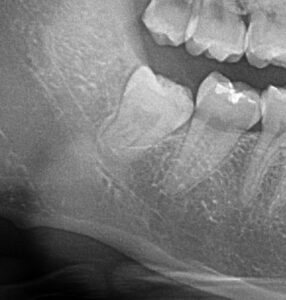

最初は垂直方向の埋伏智歯ですが、レントゲン写真を見ると比較的易しそうに見えたのですが、歯肉を剥離してみたらほとんど骨の中に埋もれていて骨削除、骨削除で結構大変でした。